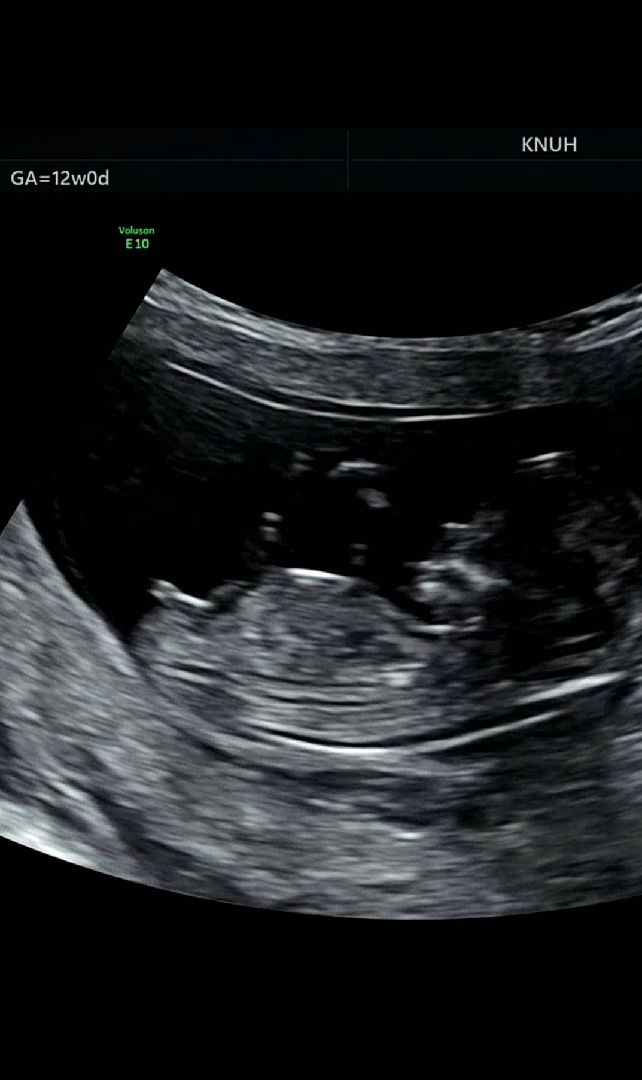

12주차 각도법??

각도법으로 보기 전에 너무나도 하얀게 선명하게 보이네용??? 아님 저거 뼈일까요?? 각도법 고수님들 한번 봐주세용!

발인것같아요

저거 🌶️ 맞는거 같기도 해요 저도 오늘 촘파 보고왔는데 저랬거든요 ㅋㅋ

앜ㅋㅋㅋ그럴까요..? 저희 남편이 🌶가 저렇게 클 수가 없다며 부정중인데 ㅋㅋㅋ3주 뒤를 기다려봐야겠어요

딸같은데용????